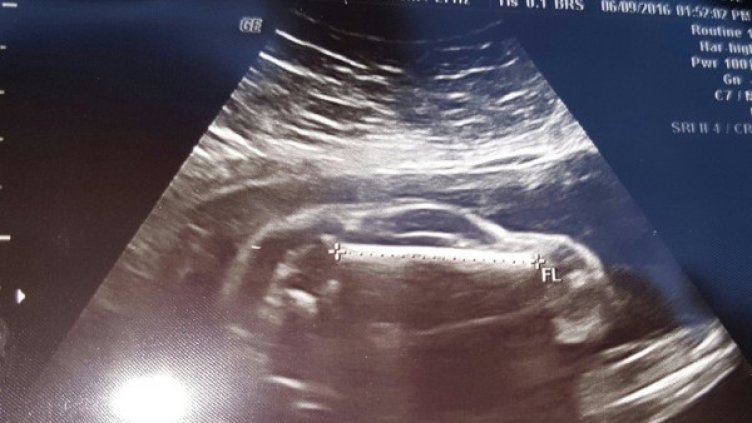

За обикновения човек ултразвукът не показва много - вижда се някакво сиво петно, което вероятно е бебе, но това е всичко. След това всеки си го опреличава на нещо. Бяхме виждали бебета, приличащи на ултразвука на извънземни, на Спайдърмен, но един потребител на Reddit ни показа нещо невиждано досега.

"Жена ми е бременна със спортна кола", написа той. При преглед в 24 гестационна седмица ултразвукът показал изображението по-горе. Мъжът разпозвал формата веднага - бебето всъщност е малка кола.

Бъдещият баща споделя още, че с жена си имат вече дъщеря и тя не прилича изобщо на спортно превозно средство.

Жената забременяла 6 месеца след като родила първото им дете. "Случи се чудо и жена ми забременя естествено, доколкото е естествено да носиш в себе си автомобил", пише бъдещият баща.

Потребителите на Reddit кръстиха "модела" автомобил Ford Fetus. Малко по-късно бащата отново писа, за да каже, че колата ще бъде синя.